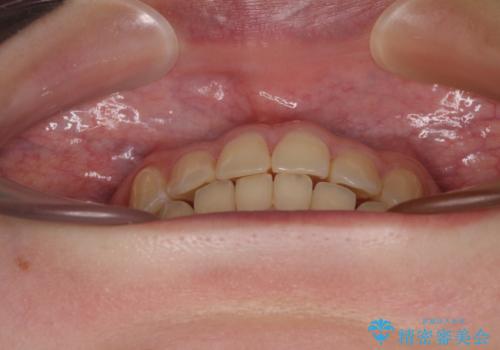

前歯のクロスバイト ギラギラのワイヤー装置で矯正治療

クロスバイトが改善する際は、前歯しか接触しないため、痛みがあったり食事が取りにくかったりと、不便な時期がありますが、1年強の短期間で無事に治療を終えることができました。